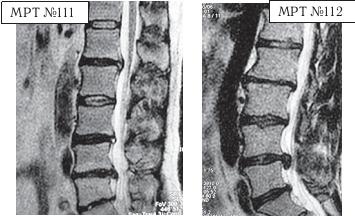

На МРТ № 108 состояние шейного отдела позвоночника пациента через 11 месяцев после дискэктомии с межтеловым спондилодезом в сегменте СIV—СV Наблюдается постхирургическая травма спинного мозга на данном уровне хирургической фрезой, кифозирование физиологического лордоза, стеноз позвоночного канала с блоком ликворных путей. На МРТ № 109 состояние шейного отдела позвоночника того же пациента через 23 месяца после дискэктомии с межтеловым спондилодезом в сегменте CIV-CV Наблюдается усугубление стеноза (абсолютный стеноз), спондилолистез (смещение вышележащего позвонка по отношению к нижележащему) СII— СIII, секвестрированная грыжа межпозвонкового диска CV—CVI. На данных снимках наглядно отображается, как подобные операции усугубляют биомеханические нарушения и тем самым способствуют развитию дегенеративно-дистрофического процесса в других сегментах позвоночника. Во время операции грыжу межпозвонкового диска в данном сегменте убрали. Но причины, которые как раз и спровоцировали образование грыжи, а именно биомеханические нарушения (дегенерация выше- и нижележащих межпозвонковых дисков, стеноз, кифоз), как были, так и остались! Несмотря на то что отдалённые последствия этой операции легко прогнозировались и полученный результат, как факт, абсолютно закономерен, подобные операции, к сожалению, как делались, так и делаются и, пожалуй, самое печальное, что и будут делаться дальше. Случаи послеоперационных рецидивов грыж межпозвонкового диска бывают разные, но причины, как правило, идентичны. Вот одна из типичных ситуаций. Врачи во главе с хирургом после хирургической операции пациента по поводу грыжи межпозвонкового диска в сегменте LV-SI в качестве профилактики посоветовали ему заниматься вытяжением позвоночника под собственным весом и укреплением мышечного корсета путём выполнения специальных упражнений на наклонной плоскости. Результат усердия пациента, последовавшего такому совету, можно наблюдать на МРТ № 110 (см. стр. 286). Исходя из анатомического и физиологического строения позвоночника человека и неизбежного действия законов физики, результат от такой «профилактики» вполне прогнозируем. Поэтому логично предположить, что врачи, посоветовавшие данному пациенту такую «профилактику», спровоцировавшую секвестрированную грыжу межпозвонкового диска в сегменте L^ — Ly, просто не знали о её последствиях. Если бы здоровье пациента позволило бы продолжить эти упражнения, то аналогичные осложнения неизбежно образовались бы и в вышележащих позвоночнодвигательных сегментах. ![]() На МРТ № 110 наблюдается состояние поясничного отдела позвоночника: секвестрированная грыжа межпозвонкового диска в сегменте LIV-LV с разрывом задней продольной связки, абсолютный стеноз спинномозгового канала. Но не спешите обвинять хирургов. Как бы это странно не звучало, это не их вина — они всего лишь удаляют часть ткани организма (грыжу). Ведь профессия хирурга заключается в знании и умении оказать пациенту своевременную хирургическую помощь, а вот послеоперационным восстановлением и «профилактикой» должны заниматься врачи-реабилитологи. Даже самые лучшие хирурги в мире, в совершенстве владеющие своей специальностью, за пределами операционной становятся обыкновенными людьми, которым, как и многим, свойственен относительный процесс познания. Требовать от них большего, это значит требовать от человека абсолютного процесса познания. Если вы считаете, что на это способен любой человек, попробуйте начать с себя. Гораздо хуже, когда врачи-реабилитологи в качестве «профилактики» дают такие «советы», вот это уже можно назвать профессиональной безграмотностью. Вот ещё случаи послеоперационных рецидивов грыж — естественной реакции организма, когда проблема решается однобоко — всего лишь с помощью хирургической операции в поражённом сегменте без общего восстановления биомеханики позвоночника.